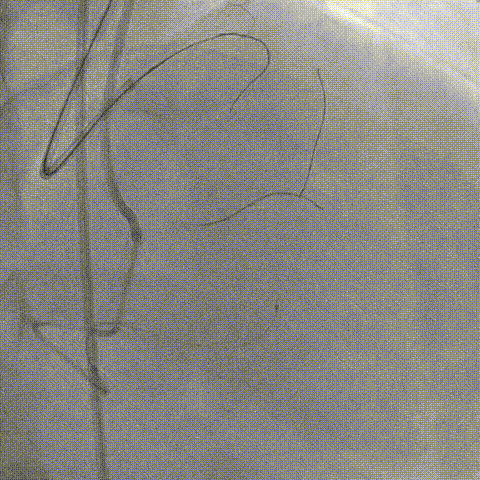

手术影像

LAD开口全闭、OM开口70%

LM未见狭窄、LCX近中段40-50%狭窄

RCA 近段 60%、中段重度迂曲

LAD pre-IVUS check RUN 1 looking for entry point

LAD SPB 3.5 SH, Sasuke, 正向尝试 Judo 1, Judo 3, Judo 6, CP, CP 8-20

正向导丝穿刺、严重钙化、走行困难

对侧造影提示导丝行至内膜下